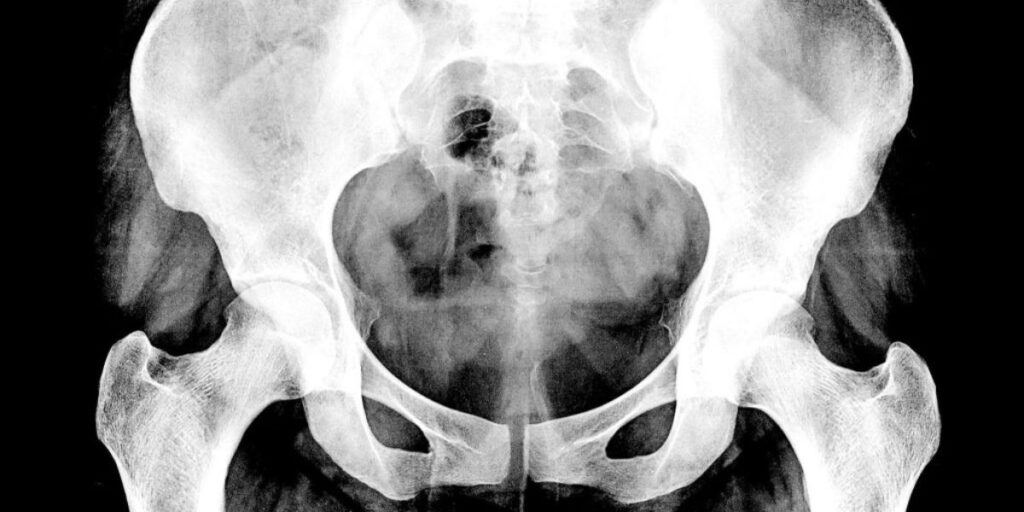

L’Esame RX dell’Anca è una procedura diagnostica che sfrutta i raggi X per creare immagini dettagliate dell’articolazione dell’anca. Nel nostro poliambulatorio, siamo specializzati nell’esecuzione di questo esame, avvalendoci delle tecnologie più avanzate e di un team di professionisti altamente competenti.

Questa procedura non invasiva consente di esaminare l’anatomia dell’articolazione dell’anca grazie ai raggi X. Presso il Poliambulatorio S-Medical Group di Sora, forniamo un ambiente confortevole e accogliente per i pazienti che necessitano di questo esame. Il nostro personale di radiologia, esperto e qualificato, eseguirà l’esame con la massima attenzione e professionalità.

L’Esame RX dell’Anca si basa sul principio della radiografia, in cui i raggi X attraversano il corpo. Presso il nostro poliambulatorio, dotato delle tecnologie più moderne, le immagini radiologiche vengono acquisite e visualizzate su schermi ad alta definizione. Il nostro team di radiologi, appartenente al Poliambulatorio S-Medical Group di Sora, esamina attentamente queste immagini per valutare la salute dell’anca del paziente.

Grazie all’Esame RX dell’Anca, possiamo osservare dettagliatamente l’anatomia dell’articolazione. Presso il Poliambulatorio S-Medical Group di Sora, utilizziamo questo esame per identificare eventuali anomalie o lesioni. Le immagini ottenute chiaramente mostrano le strutture ossee dell’anca, come l’acetabolo e il femore. Questo ci consente di analizzare l’usura dell’articolazione e identificare fratture, deformità o segni di infiammazione.

L’Esame RX dell’Anca è un procedimento semplice e rapido, eseguibile presso il Poliambulatorio S-Medical Group di Sora. Il paziente viene posizionato sul tavolo radiografico in diverse posizioni, al fine di ottenere immagini esaustive dell’articolazione da varie angolazioni. I nostri tecnici qualificati garantiscono un posizionamento accurato e confortevole, assicurando la qualità delle immagini.